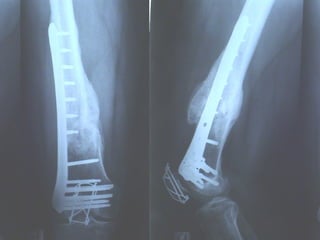

Dal Gennaio 2000 al Dicembre 2005 27 placche LISS di femore

INDICAZIONI COMUNI Fratture sovracondiloidee Fratture intercondiliodee Fratture diafisarie distali PARTICOLARI Fratture con grave osteoporosi Fratture periprotesiche

VANTAGGI CHIRURGIA MININVASIVA Mini Open Inserimento della placca sottocutaneo per scivolamento Viti percutanee Preservazione dei tessuti molli Ridotto danno vascolare Rapida ripresa funzionale

F, 68 y

LISS  NCB

NCB

Conclusioni Riduzione  anatomica Minimo trauma chirurgico Corretto equilibrio fra elasticità e stabilità Precoce mobilizzazione